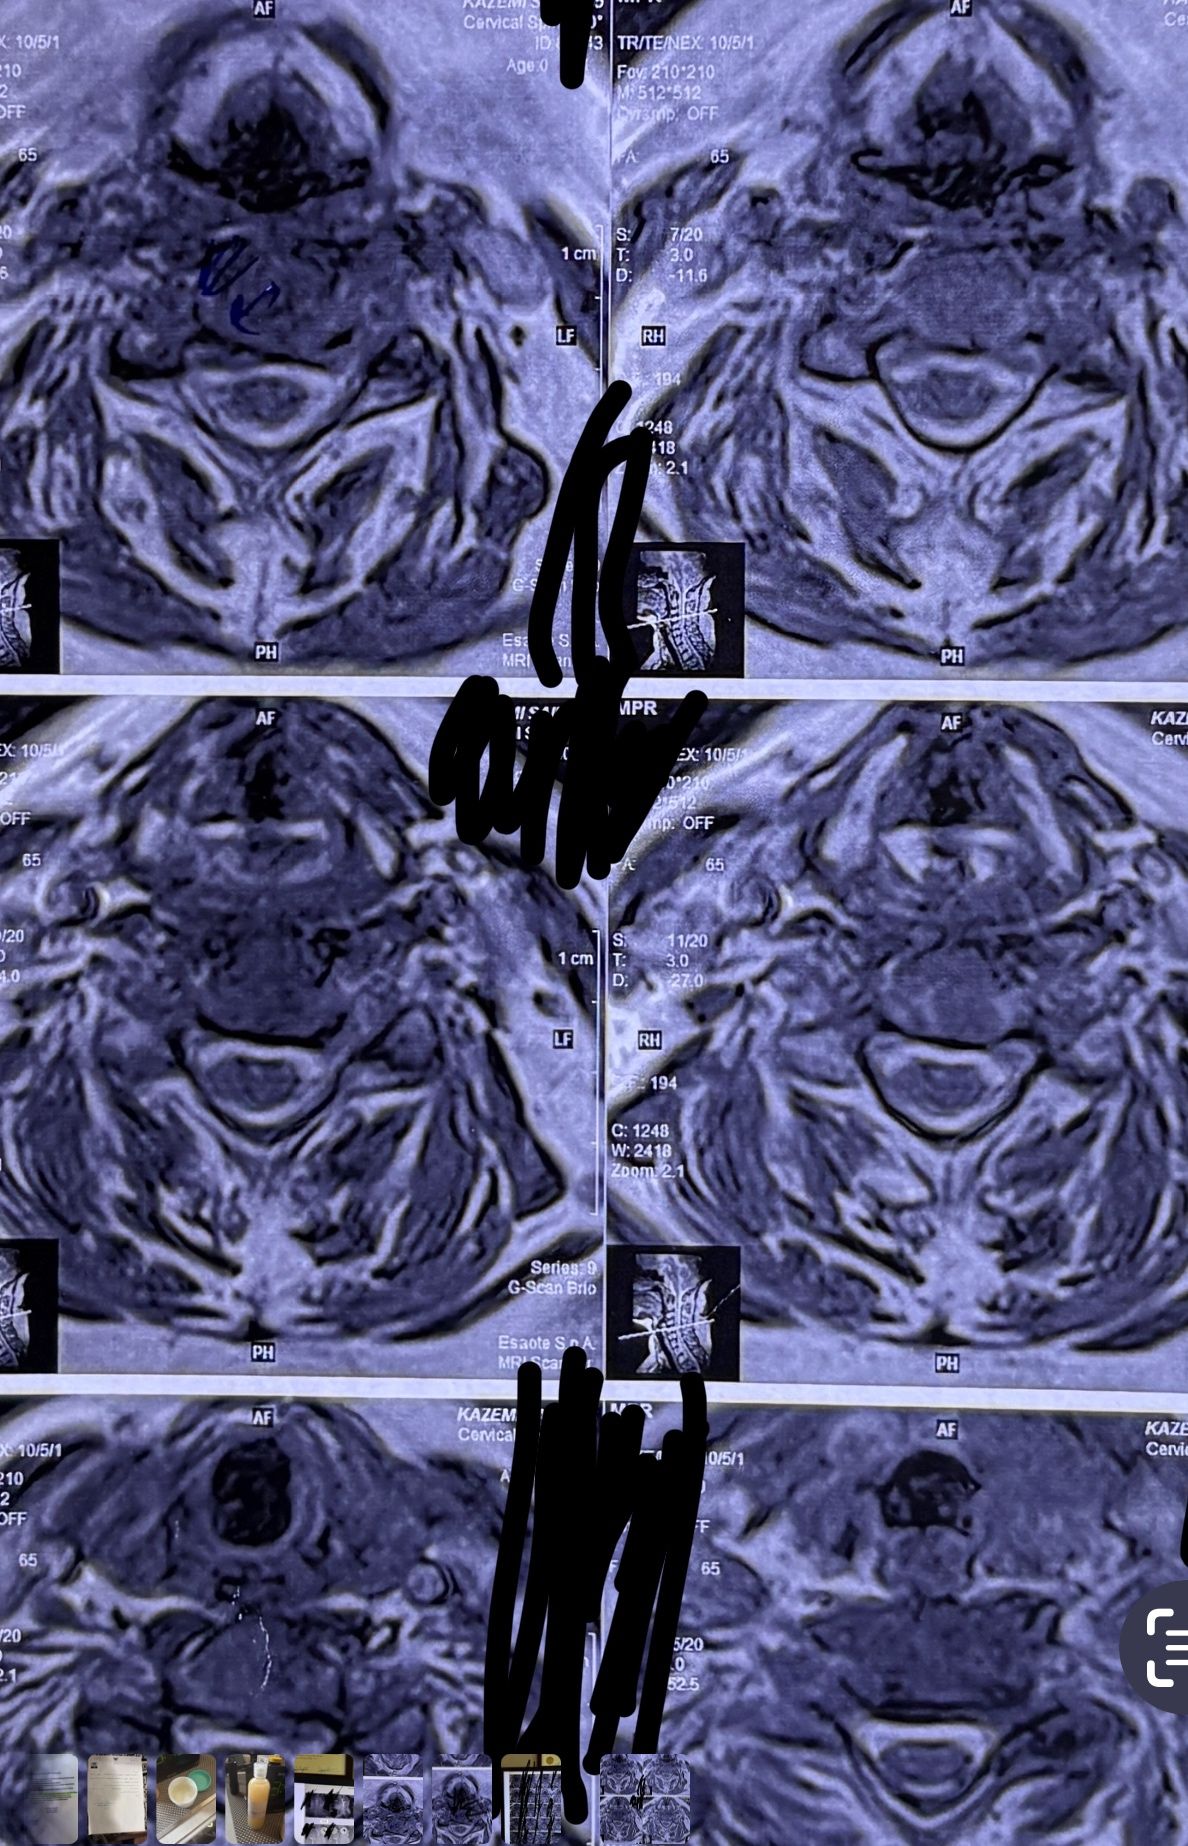

41 years old man presented to my clinic in October 2023 with acute and sever R neck pain with radicular pain to his R upper extremity along C6 dematom since 2 weeks ago. Examination didn’t show any upper motor signs. Was suggested urgent surgery

I ordered EMG/ NCV : showed mild R C6, C7 irritation without any active axonal loss

In his MRI was reported R. para R. IVF Massive extrusion. I decided to control his pain and manage this patient with reevaluation of patient every other session. For 5 sessions i just used acupuncture and laser and IFC and mild adjustments to his R. T3-T7 and mild arthosteem to above and below involved segment. Cervical adjustment considered contraindicated for this patient. From session 6th- 8th i started to use mild/gentle cervical decompression. He used soft cervical collar all the time. His pain decreased by 80 percent

I gave him cervical traction pump to be used 3-5 times per day at home for the next 3 months and i released the patient. He was evaluated every week once for one month and after that every 2 weeks. After 3 month I repeated MRI. Size of the herniated disc was reduced greater than 50 percent. Asked him to do another mri in 6 months

MRIs before and after proper management of this patient: